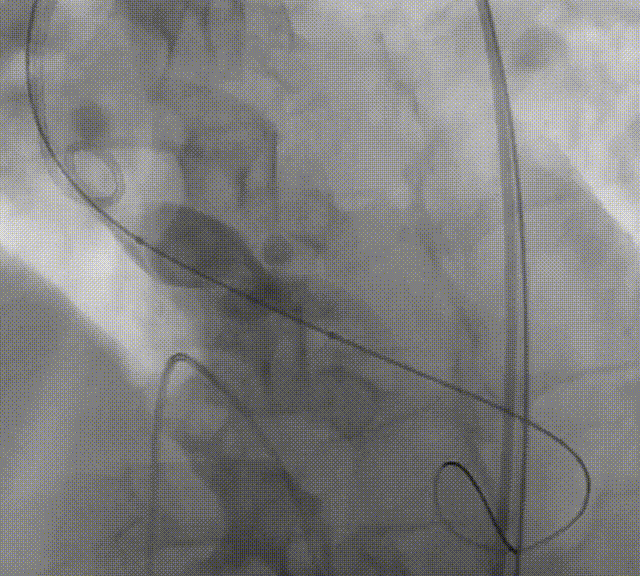

定位

初始定位

预释放后定位

首次释放弹出

再次释放

深度评估

1、起始释放位置建议Hat Marker在猪尾环中间位置往下,接近猪尾底部的位置;

2、当瓣膜与capsule扩张口齐平即将“开花”时,需确认瓣膜位置在自体瓣环平面以下;

3、最终植入深度建议为5mm。

在评判植入深度是否合理时,应特别关注瓣架形态,特别是瓣架底部扩张形态。如底部呈现“收口”形态,应谨慎评估植入深度,必要时回收瓣膜,调整为更深的释放位点;